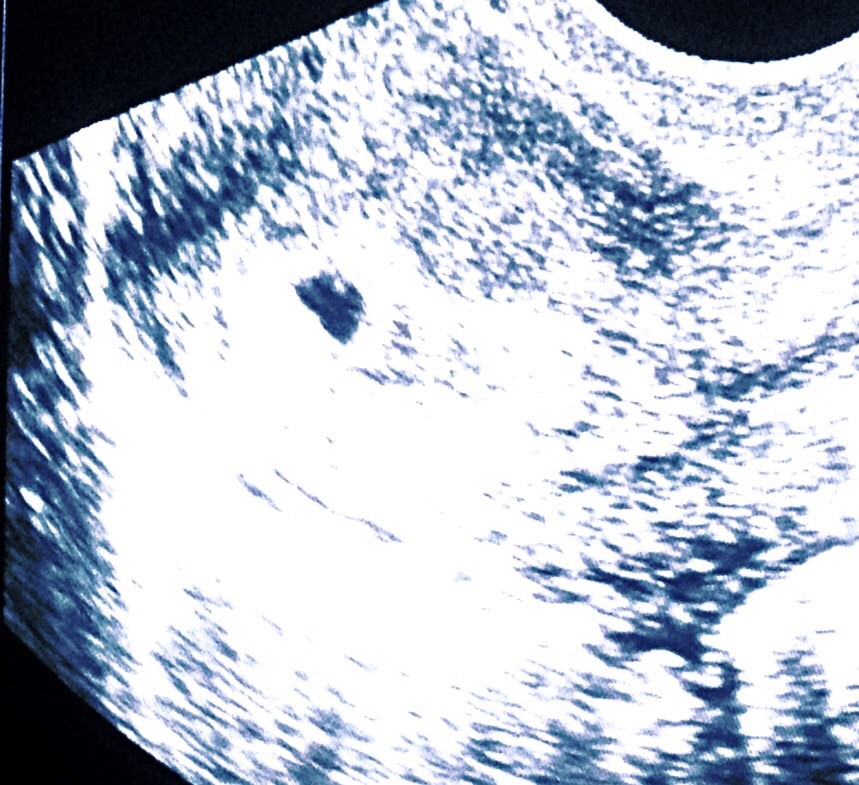

total udorventet . Så ingen ved rigtig hvor langt jeg er ud over den scanning de lavede og beregnede ca at jeg var 4+3 i onsdags

Vedhæftede fotos (klik for at se i fuld størrelse)